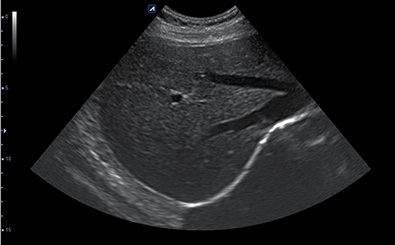

CLINICAL IMAGES

臨床影像

Abdomen